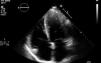

In March 2013 he began to experience fatigue, dyspnea on moderate and mild exertion, abdominal swelling, lower limb edema and cachexia. He was medicated with furosemide and ivabradine and assessed by a cardiologist four months after symptom onset. On physical examination he was in New York Heart Association (NYHA) class III, with marked weight loss and venous jugular distention; bilateral basal rales on pulmonary auscultation; rhythmic S1 and S2 on cardiac auscultation with a grade III/VI aortic early to mid systolic murmur radiating to the carotids; palpable hepatomegaly 4 cm below the costal margin; moderate ascites and lower limb edema up to the knee. The electrocardiogram showed sinus rhythm and complete right bundle branch block. On the chest X-ray cardiomegaly was visible with right atrial dilatation and bilateral hilar enlargement. Laboratory tests revealed anemia (hemoglobin [Hb] 9.9 g/dl). The echocardiogram showed dilatation of both atria and the right ventricle (RV) (Figure 1), with mild hypertrophy of the ventricular septum; a thickened and calcified aortic valve with significantly limited opening (Figure 2); peak left ventricular (LV)/aortic gradient of 55 mmHg, mean 33 mmHg, and functional aortic valve area of 0.8 cm2 (0.39 cm2/m2); mild to moderate tricuspid regurgitation (Figure 3) with pulmonary artery systolic pressure (PASP) of 51 mmHg; mild to moderate LV systolic dysfunction; systolic and diastolic straightening of the ventricular septum; and impaired RV systolic function.